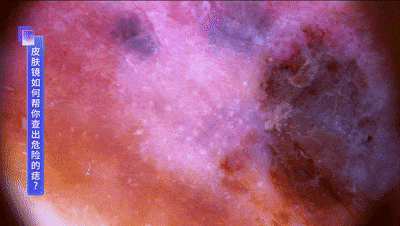

而恶性的黑色素瘤,就会有不规则的蓝白结构、丰富的血管供应等特征↓